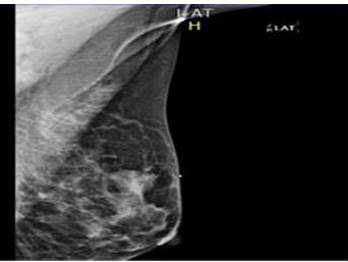

En mamografía izquierda se evidencia lesión irregular, de contorno espiculado con calcificaciones dispersas en UCS de mama izquierda, BIRADS 4C y la biopsia con aguja gruesa reporta: carcinoma ductal infiltrante bien diferenciado, estudios de extensión sin alteraciones. Se decide llevar a mesa operatoria para mastectomía parcial oncológica (MPO) con corte congelado (CC) y ganglio centinela (GC) con azul patente.

En la mamografía, los MpBC muestran muchas similitudes con el IDC, En el caso actual, la paciente presentó lesión de crecimiento acelerado, en cuya mamografía se evidencia imagen espiculada con calcificaciones sugestivas de malignidad en UCS de mama izquierda, sin adenopatías axilares (Figura 5 y 6).